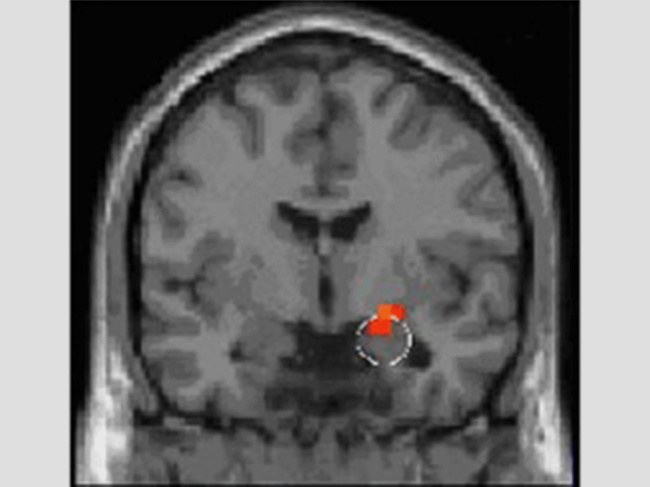

Amygdala

As research reveals brain disease circuitry, targeting follows suit

Attempts to modernize the conceptual framework of brain function and dysfunction are one prerequisite for brain disorders to benefit from precision medicine. For the circuit-based insights that are slowly emerging to benefit patients, though, better targeting methods are needed. Read More